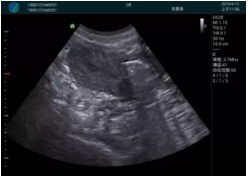

M20便攜超聲在臨床中的應(yīng)用:

可視化穿刺引導(dǎo)

M20實時引導(dǎo):向包塊后方間隙注射利多卡因

清晰顯示腺體內(nèi)低回聲快影,邊界清晰,包膜較光滑

確定進針路徑并實時監(jiān)測抽吸針與腫塊位置關(guān)系

抽吸針進入腫塊內(nèi)部進行旋切

抽吸過程中可見腫塊明顯縮小,并根據(jù)腫塊位置改變針道位置

抽吸旋切后再進行超聲復(fù)查,原腫塊區(qū)域未見殘留組織及出血

超聲引導(dǎo)下抽吸旋切取出的腫塊組織

病例二:

腺體內(nèi)部清晰顯示一低回聲塊影,形態(tài)不規(guī)則,邊界模糊,邊緣呈毛刺狀,內(nèi)部見砂礫樣鈣化

M20引導(dǎo)下穿刺活檢術(shù)

M20引導(dǎo)下平面內(nèi)穿刺取出的腫塊組織

M20查看:囊內(nèi)回聲均勻,邊界清晰,囊壁光滑

M20引導(dǎo)抽吸術(shù)后囊腫消失,原區(qū)域空腔形成,脂肪層與腺體層架構(gòu)發(fā)生改變

超聲以操作簡單、定位準確、實時顯像、費用低廉等優(yōu)勢,而成為麥默通乳腺活檢治療乳腺腫塊最常見的引導(dǎo)手段,已逐步在各大醫(yī)院開展此類手術(shù)。

2、超聲的可視化操作,能準確的顯示病灶的位置、最大徑,選擇合適的刀具,決定切口的位置和方向,避開血管、減少出血危險并實時觀察乳腺病灶的切割情況,避免造成腫塊組織殘留